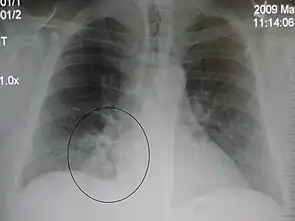

Right upper lobe pneumonia as marked by the circle. Left upper lobe pneumonia with a small pleural effusion.

Left upper lobe pneumonia with a small pleural effusion. Right lower lobe pneumonia as seen on a lateral CXR

Right lower lobe pneumonia as seen on a lateral CXR